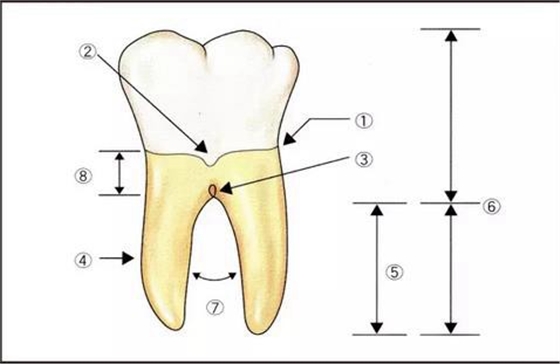

根分叉部周圍的基本名稱:

▼圖1各部位的名稱

??釉牙骨質(zhì)界

??釉突

?釉珠

?牙根的形態(tài)

?牙根的長度

?牙冠-牙根比

?牙根的離開度

?根柱的長度